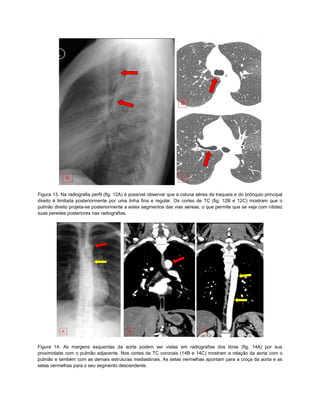

Figura 13. Na radiografia perfil (fig. 12A) é possível observar que a coluna aérea da traqueia e do brônquio principal

direito é limitada posteriormente por uma linha fina e regular. Os cortes de TC (fig. 12B e 12C) mostram que o

pulmão direito projeta-se posteriormente a estes segmentos das vias aéreas, o que permite que se veja com nitidez

suas peredes posteriores nas radiografias.

Figura 14. As margens esquerdas da aorta podem ser vistas em radiografias dos tórax (fig. 14A) por sua

proximidade com o pulmão adjacente. Nos cortes de TC coronais (14B e 14C) mostram a relação da aorta com o

pulmão e também com as demais estruturas mediastinais. As setas vermelhas apontam para a croça da aorta e as

setas vermelhas para o seu segmento descendente.